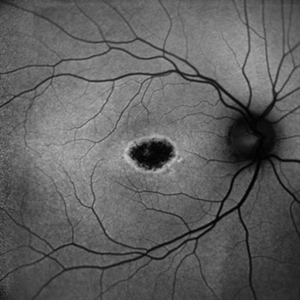

Macular Dystrophy Macular DystrophyNov 3 2023 by Anjana Mirajkar, MS Ophthalmology An autofluorescence image -OD of a 22 year old male case of macular dystrophy showing hypo autofluorescence Photographer: Dr. Anjana Mirajkar -Retina Foundation, Ahmedabad Imaging device: Mirante-Nidek Condition/keywords: heredomacular degeneration, Macular Dystrophy